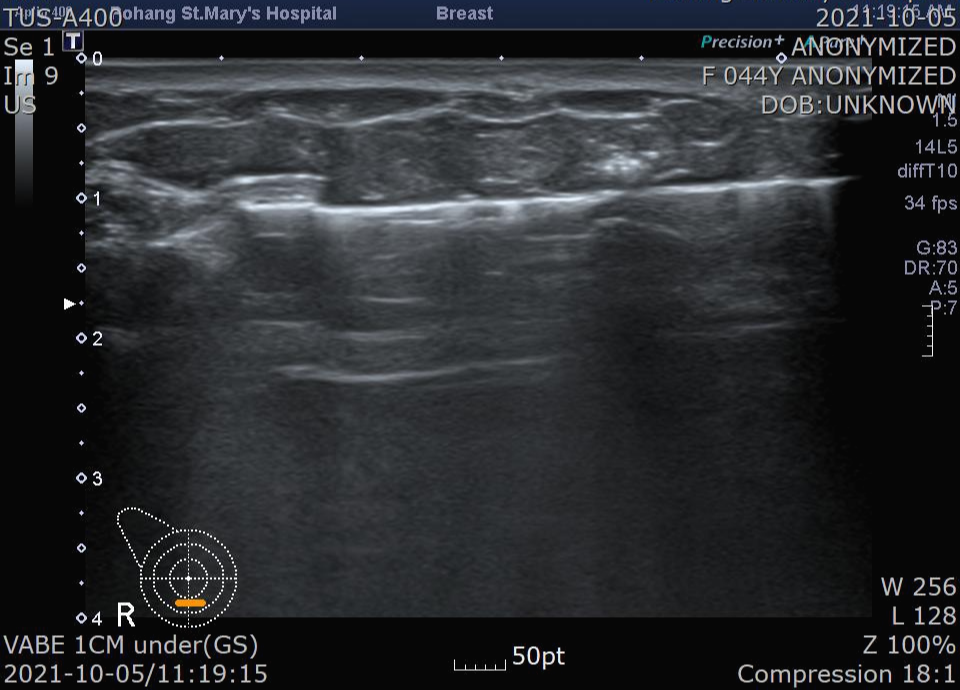

또 자릅니다. 이작업을 여러번하는데 결국 조직이 깨끗하게 잘 제거된 모습을 확인할 수 있습니다.

이 환자는 조직검사에서 양성 종양으로 확인되어 정기적인 추적 관찰만 하면됩니다.